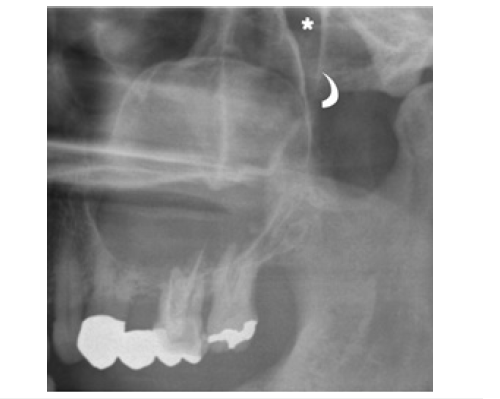

Figure 2:

A cropped panoramic radiograph of the posterior left maxilla shows a large OKC extending into the maxillary sinus (arrows). The posterior wall of the maxillary sinus (curved arrow) and the pterygopalatine fossa (asterisk) are also visible. Radiographically, OKCs may cause tooth displacement and, less commonly, root resorption. Root resorption is considered an uncommon feature, with reported incidences ranging from 1.3% to 11% [9]. The literature indicates that cortical bone perforation is not unusual in OKCs, with intraoperative reports ranging from 39% to 51% [9]. However, this feature is rarely detectable on panoramic radiography and when present, is generally confined to the alveolar crest.